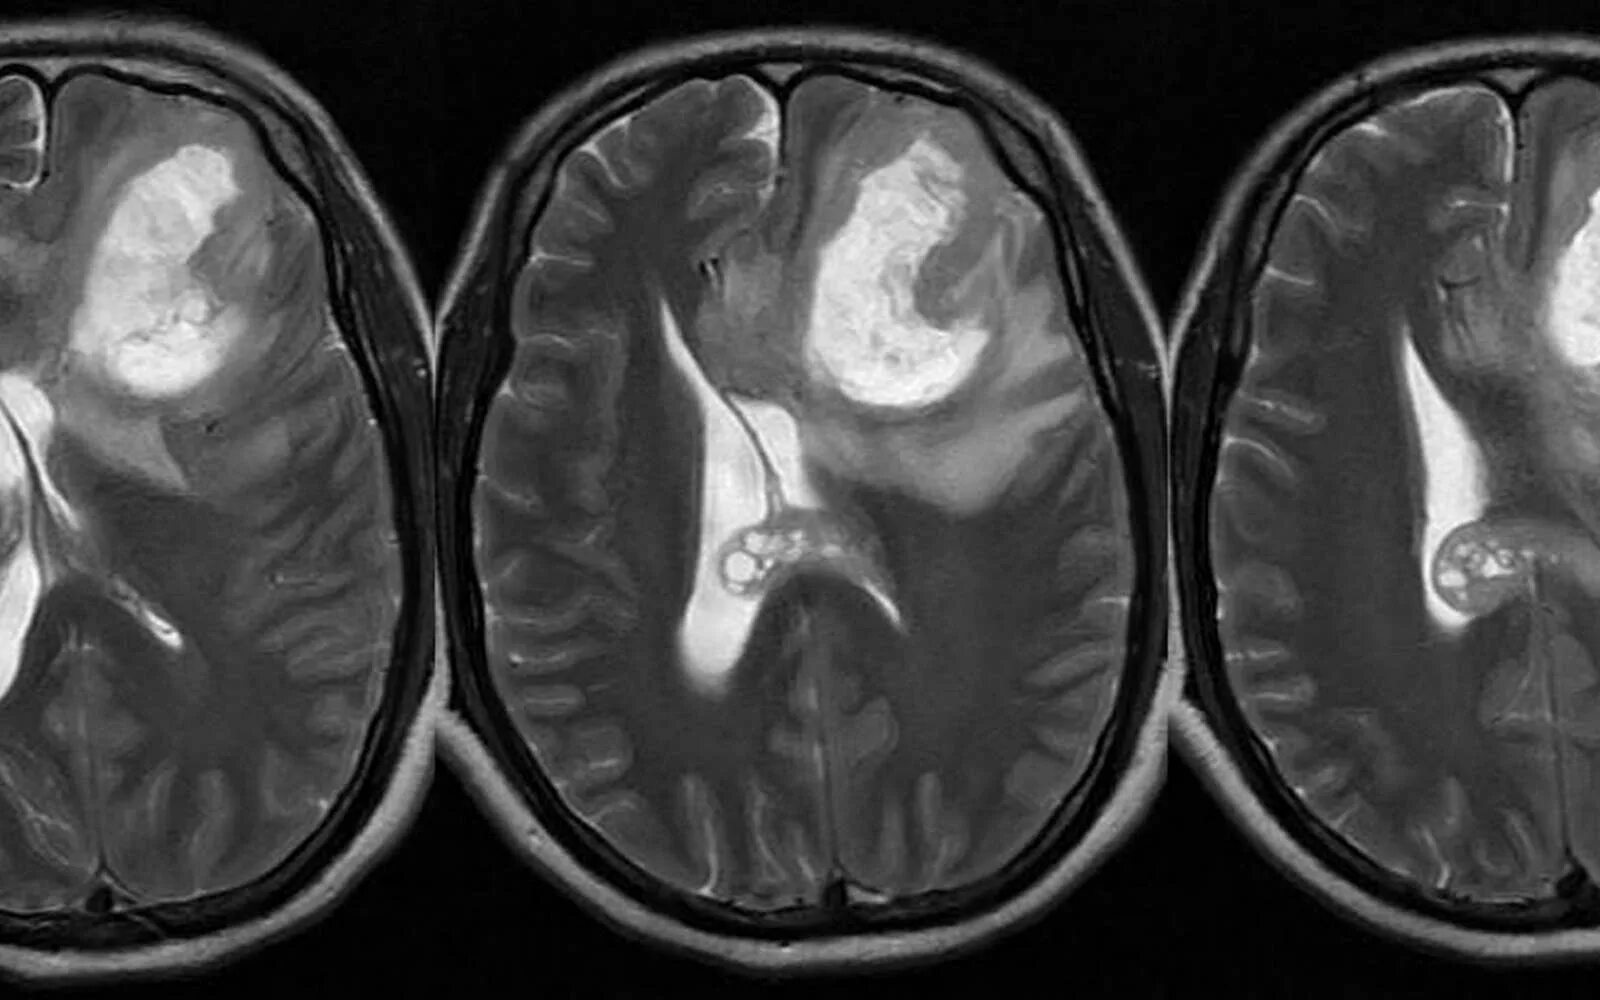

Стадии рака мозга симптомы